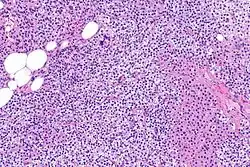

Parathyroid hyperplasia medium mag.

Parathyroid glands are normally composed of chief cells, adipocytes and scattered oxyphil cells.[27][14] Chief cells are thought to be responsible for the production, storage and secretion of parathyroid hormone. These cells appear light and dark with a prominent Golgi body and endoplasmic reticulum. In electron micrographs, secretory vesicles can be seen in and around the Golgi and at the cell membrane. These cells also contain prominent cytoplasmic adipose.[27][14] Upon onset of hyperplasia these cells are described as having a nodular pattern with enlargement of protein synthesis machinery such as the endoplasmic reticulum and Golgi. Increased secretory vesicles are seen and decreased intercellular fat is characteristic.[27][24] Oxyphil cells also appear hyperplasic however, these cells are much less prominent.

Parathyroid hyperplasia high mag.